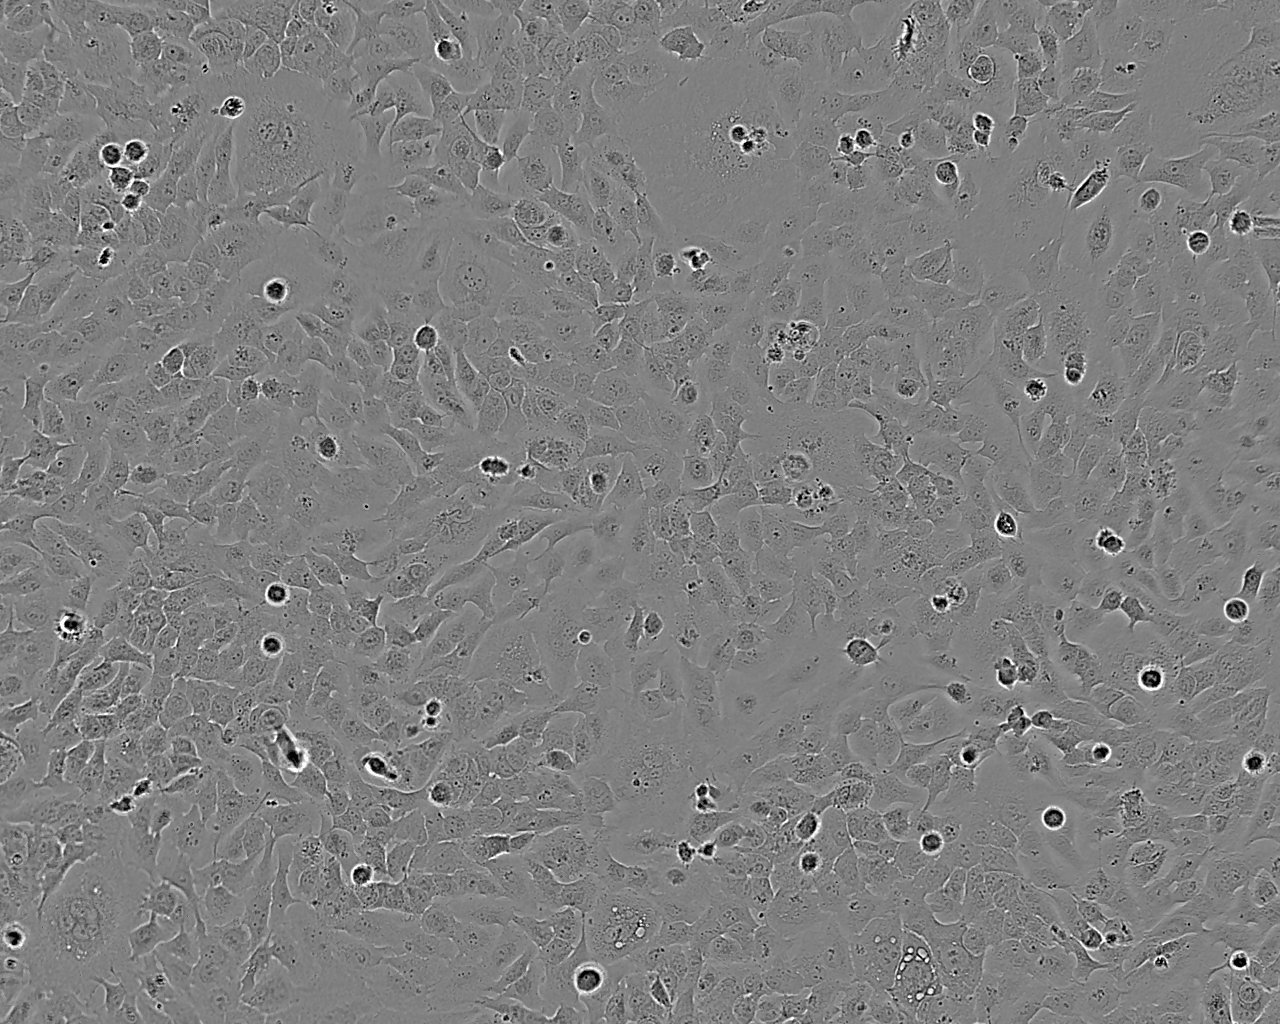

Images

SK-GT-4 was established from a primary tumour in 1989 from a 89 year-old Caucasian male who presented with dysphagia secondary to a well-differentiated adenocarcinoma arising in the Barrett epithelium of the distal oesophagus. The tumour invaded into but not through the muscle layer (T2) and involved 3 of 14 lymph nodes (N1). SK-GT-4 was found to be tumorigenic in athymic nu/nu mice.Cultures derived from ECACC stocks of this cell line have been whole genome sequenced (Contino et al 2016) confirming the presence of many of the known mutations that drive oesophageal cancer